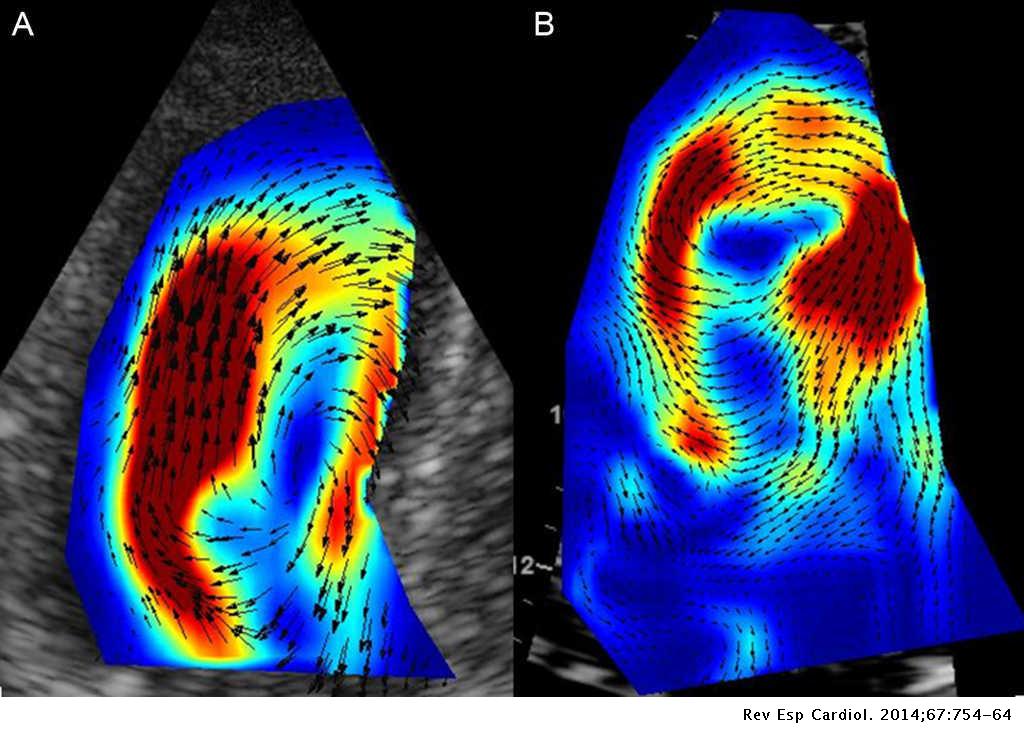

Imaging Techniques In The Evaluation Of Post Infarction Function

Imaging Techniques In The Evaluation Of Post Infarction Function

Imaging Techniques In The Evaluation Of Post Infarction Function